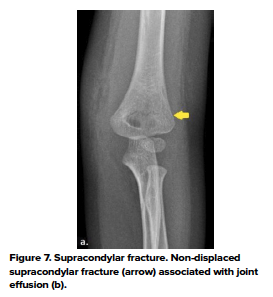

- Supracondylar fractures

- The most common pediatric elbow fracture is the supracondylar fracture, accounting for 50%-70% of cases, with a peak age of 6-7 years old.8 At this age, significant bony remodeling of the supracondylar process occurs, causing cortical thinning and predisposing to fracture. Falls onto an outstretched hand account for 95% of supracondylar fractures, causing hyperextension stress on the elbow.8 The severity of a supracondylar fracture is identified using the Gartland classification, which is helpful in delineating management. Important complications of supracondylar fractures include neuropraxia (including anterior interosseous nerve, radial nerve, and ulnar nerve palsies) and vascular compromise. (Fig 7)